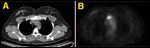

FIGURE 1

CT and PET Images From the Time of Original Diagnosis

The patient requested CT/PET imaging as part of her preoperative evaluation. This scan revealed a metabolically active lytic lesion in the manubrium of the sternum (Figure 1). Several different radiologists were consulted, and opinions differed as to whether or not this likely represented a metastatic lesion. After reviewing the case with several radiologists, the surgeon chose to proceed with definitive surgery and monitor the sternal lesion.